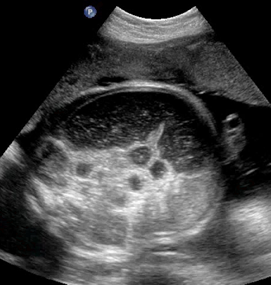

Above. Meconium peritonitis. Case 1. 36 6/7 weeks gestation. Transverse small bowel. Note small bowel dilatation and polyhydramnios.

Above. Meconium peritonitis. Case 1. 36 6/7 weeks gestation. Longitudinal small bowel. Note small bowel dilatation and mesenteric calcifications.

Above. Meconium peritonitis. Case 1. 36 6/7 weeks gestation. Again, note small bowel dilatation and mesenteric calcifications.

Above. Meconium peritonitis. Case 1. 36 6/7 weeks gestation. Note hepatic capsular calcifications and the presence of fetal ascites.